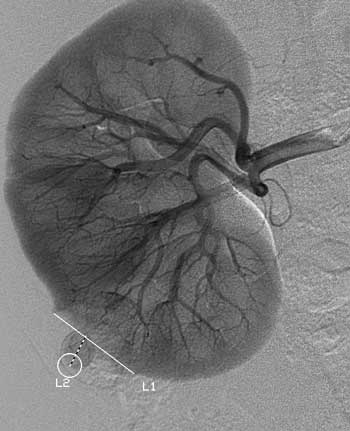

Рис. 7. Рак правой почки. Т1N0M0. Внутри округлого аваскулярного образования (дистанция L1) определяется гиперваскулярный узел (дистанция L2). VII тип васкуляризации.